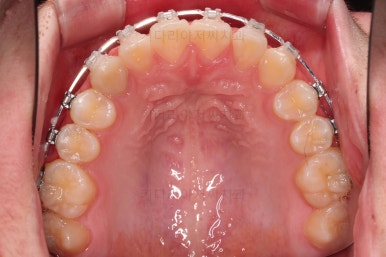

동래교정치과 초진 시 입안의 모습입니다.

치아가 벌어진 것도 벌어진 것이지만 교합이 전혀 안되고 있었어요.

틈새도 아랫니에 훨씬 많았고요.

윗니가 있는 위턱뼈가 전반적으로 아래턱에 비해 3차원으로 작은 양상이었습니다.

이번 환자분은 아랫니가 전반적으로 앞이든, 뒤든, 양옆으로든 넓어져 있는 양상이었고 그래서 아랫니에 틈도 많고 아래 앞니도 밀려나와 있는 양상인거죠.